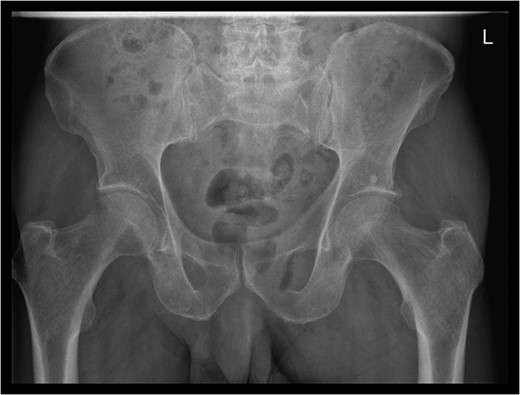

Examination revealed a 2 cm area of tender erythema and induration over the left buttock/peri-anal region. There was also some bony tenderness noted on palpation of the left hip. Rectal examination was unremarkable.

An emergency Hartmann's procedure was performed under general anaesthetic through a lower midline incision as well as lay open of the perineal fistula. On opening the abdomen, a perforated diverticulum was identified extending into the left lateral pelvic wall. A standard Hartmann's procedure was performed, with sigmoid colectomy, division of rectum at recto-sigmoid junction and a tension-free stoma formed in left hypochondrium. The left buttock abscess cavity extended by a further 2–3 in. and the cavity then packed.